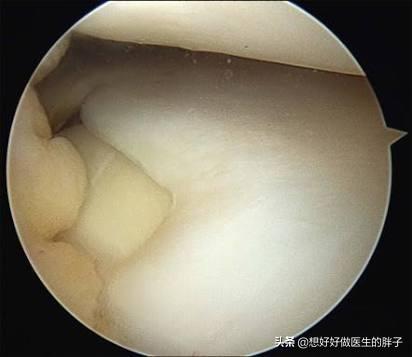

另外髌骨软骨软化比较经典的症状就是打软腿了。在走路的时候并没有什么特殊的诱因,膝盖会突然软一下,仿佛失去了对膝盖的控制一样。这个时候往往并不伴有疼痛,所以也很少有人在意,但是当症状越来越重,出现疼痛的时候再进行治疗可能就错过了治疗的最佳时机了!下图就是髌骨软骨不同程度软化的关节镜下影像学资料,看完之后,大家可能会对这个问题有一个更深的了解吧。

常见的导致关节内存在游离体的病因,多数是由于关节受到外伤以后,关节腔的软骨脱落到了关节腔内,有的时候这些脱落的软骨会慢慢的被磨损吸收掉,而有的时候这些软骨会慢慢变成钙化形成游离体。(下图就是软骨破裂的影像学资料)